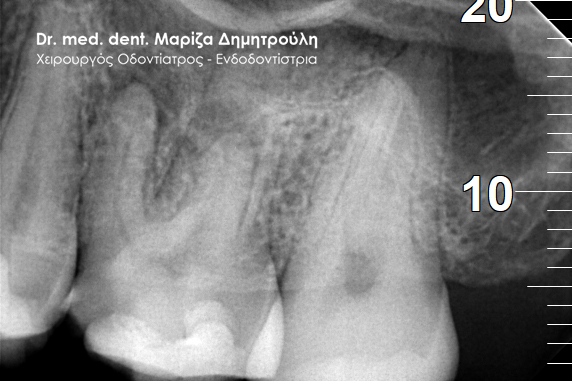

Περιστατικό – Επανάληψη απονεύρωσης δοντιού

Ο ασθενής παραπονείται για έναν μόνιμο πόνο στην περιοχή του αριστερού ιγμορείου. Ανέφερε οτι πριν χρόνια πραγματοποιήθηκε στον αριστερό γομφίο (τραπεζίτη) μία απονεύρωση. Μετά από καιρό εμφανίστηκαν τα συμπτώματα πόνου, χωρίς καμία βελτίωση. Μετά τον αποκλεισμό της ανάμειξης του ιγμορείου στη εμφάνιση των συμπτωμάτων ακολούθησε η κλινική και ακτινογραφική εξέταση του δοντιού. Η ακτινογραφία αποκάλυψε την ατελή απονεύρωση του δοντιού.

Μετά από συνεννόηση με τον ασθενή αποφασίστηκε η επανάληψη της ενδοδοντικής θεραπείας (απονεύρωσης). Ακολούθως έγινε τοποθέτηση του ελαστικού απομονωτήρα, η διάνοιξη του δοντιού και η αφαίρεση του παλιού εμφρακτικού υλικού από τις ρίζες.Επιπρόσθετα εντοπίστηκε και παρασκευάστηκε και 4ος ριζικός σωλήνας, ο οποίος δεν είχε επεξεργστεί στην πρώτη ενδοδοντική θεραπεία ( απονεύρωση ) του ασθενούς.

Διαπιστώθηκε η ενσβεστίωση 2 ριζικών σωλήνων του δοντιού (ριζών), κάτι που δεν επέτρεψε την επεξεργασία του δοντιού σε όλο το μήκος αυτών των ριζών. Παρολ΄ αυτά μετά τη δεύτερη συνεδρία ο ασθενής ανέφερε την ανακούφιση και την εξάλειψη των συμπτωμάτων, που τον ταλαιπωρούσαν τα τελευταία χρόνια.

Εφόσον το δόντι ήταν ασυμπτωματικό και ο ασθενής δεν αισθανόταν πλέον πόνο ολοκληρώθηκε η διαδικασία της απονεύρωσης με τη χρήση των μηχανοκίνητων εργαλείων και την τελική έμφραξη των ριζών του δοντιού με νέο εμφρακτικό υλικό.

ΠΡΙΝ

ΜΕΤΑ